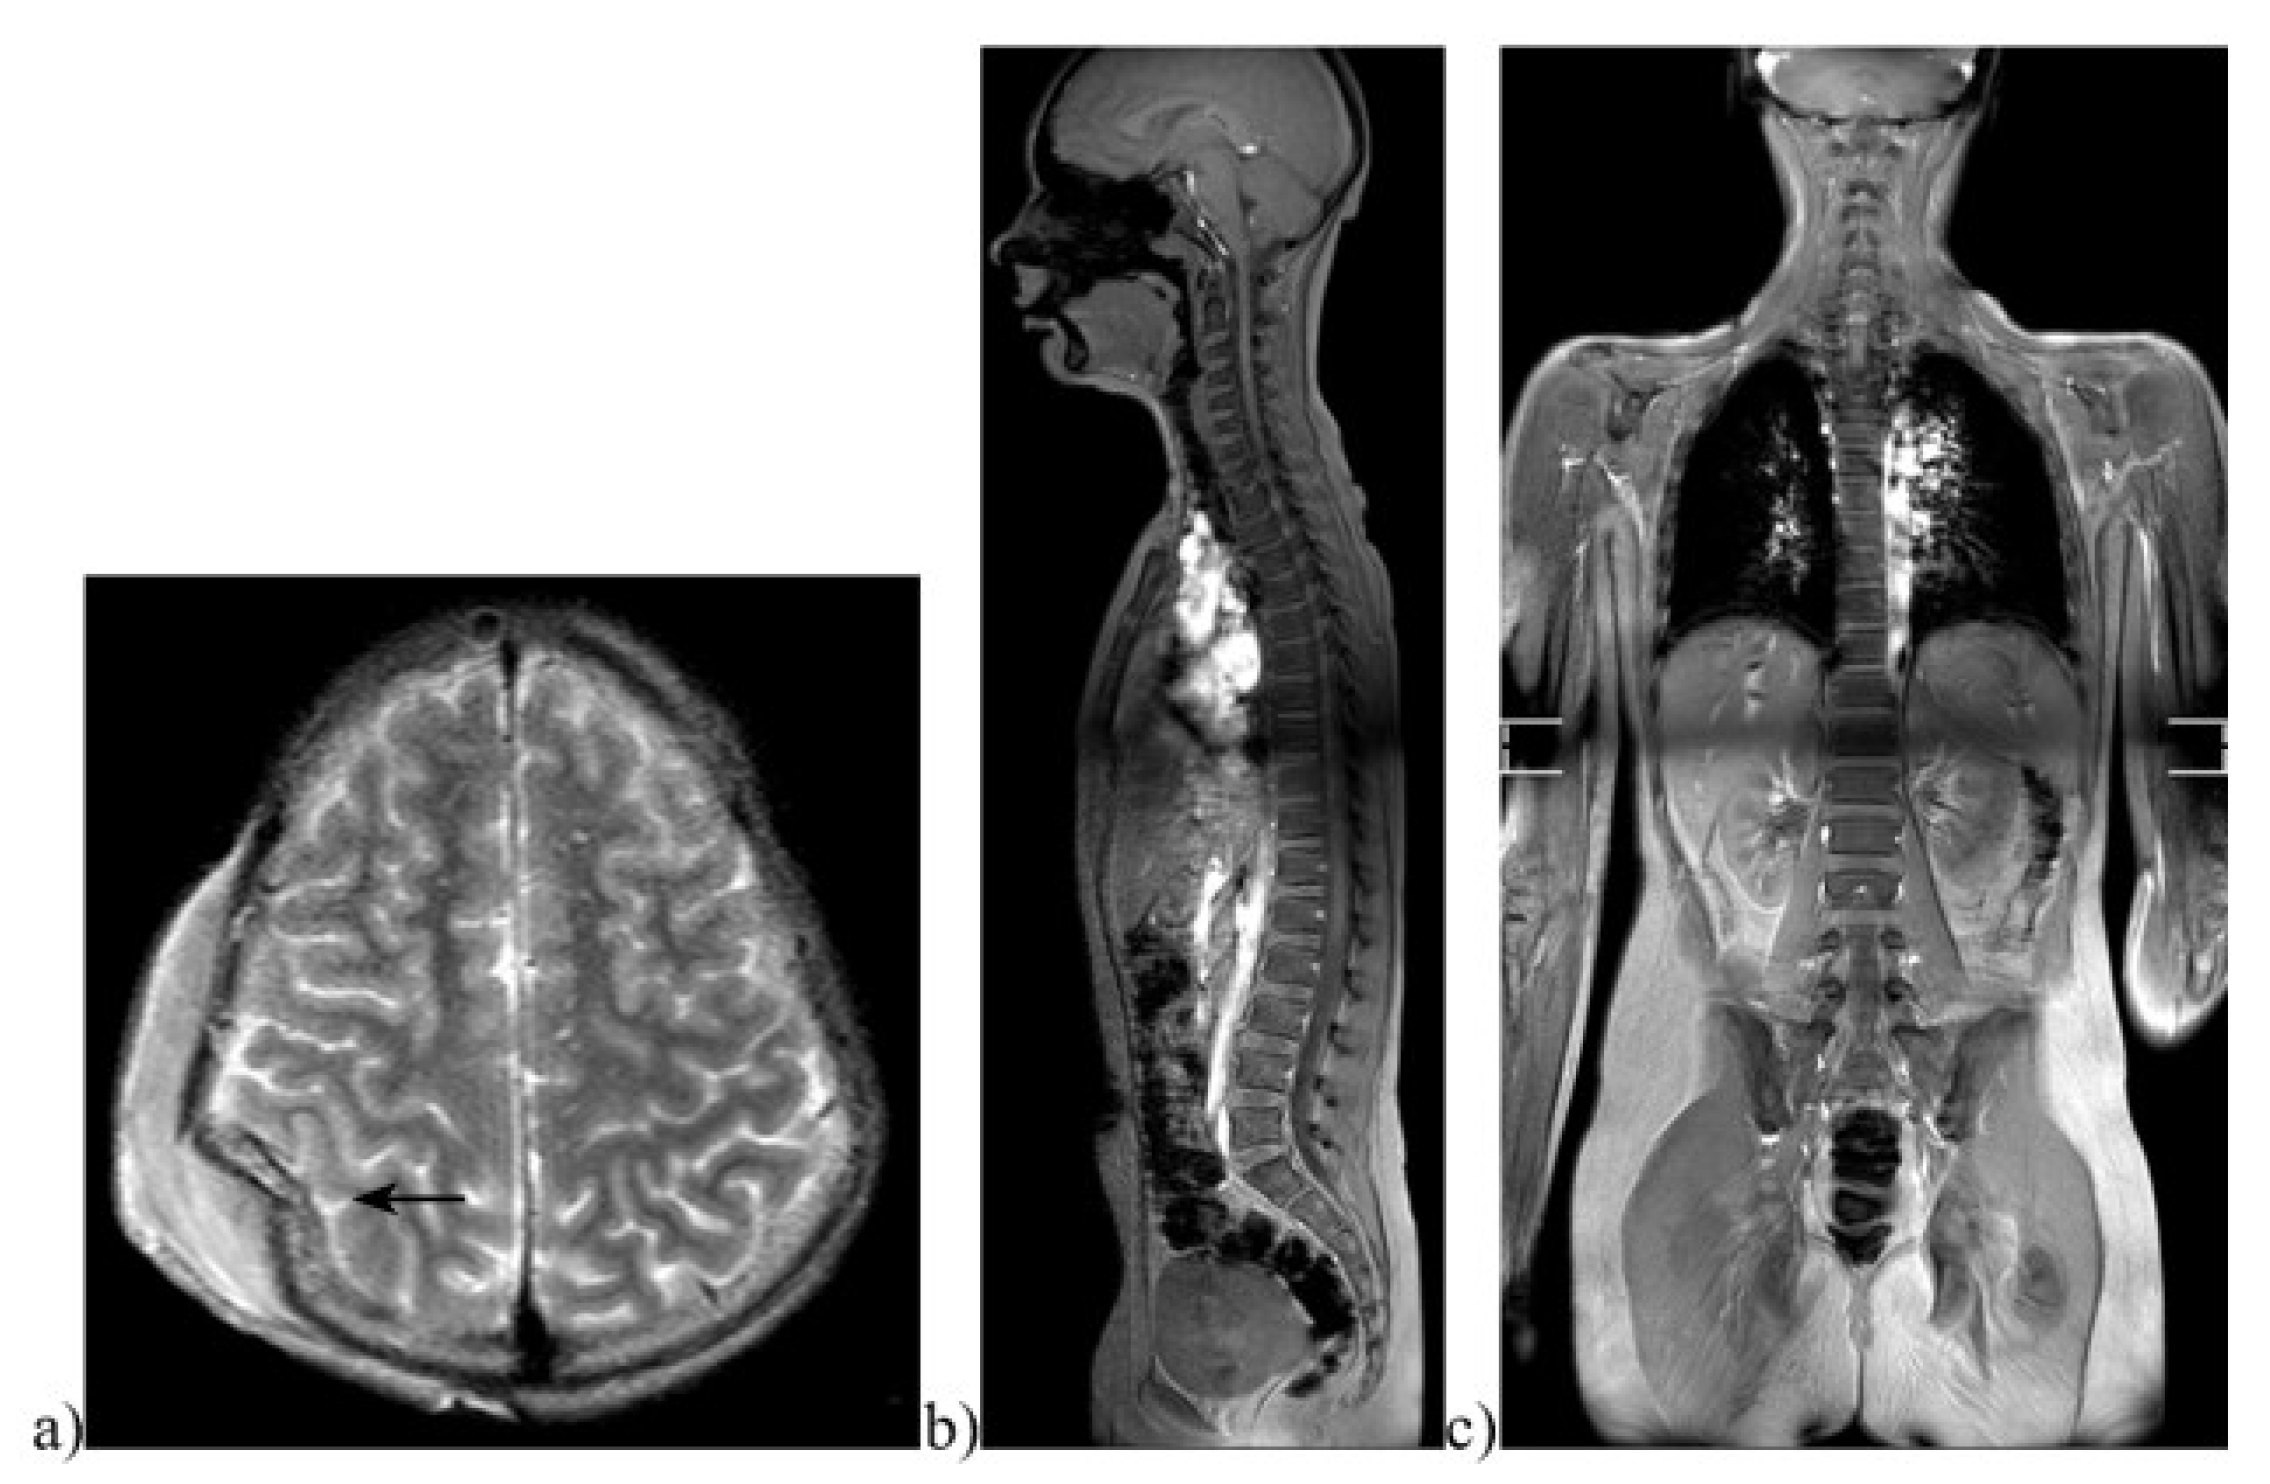

Figure 2.

Images of a pediatric whole-body magnetic resonance tomography (WBMR). Example of a 12-year-old boy who was hit by a car as a pedestrian. MRI images showing (a) a large compression fracture and subgaleal hemorrhage on axial TSE T2w imaging (marked by an arrow). The (b) sagittal STIR and (c) coronal STIR full-body images showed no spinal fracture, parenchymal lacerations, or free fluid indicating further injuries. A standard protocol developed specifically for pediatric whole-body imaging via MRI was used [17].